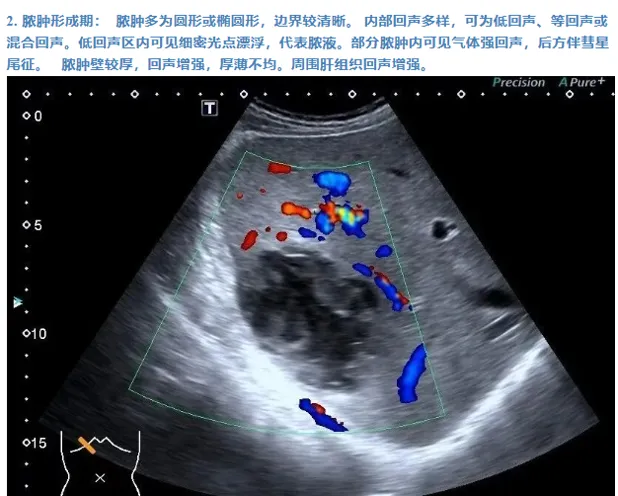

肝脓肿

● 定义:肝脓肿是肝脏的化脓性炎症,可由细菌、真菌或阿米巴原虫等感染引起。病理过程通常包括炎症浸润期、脓肿形成期和脓肿吸收期。

● 超声表现:

1.肝内单个或多个占位性病变。

2.早期呈低回声,边界不清,血流丰富。

3.脓液形成后,呈液性暗区,壁厚薄不均,内壁不平整,内透声差,可见絮状回声,有些可见分层。

4.肝脓肿进一步发展,内透声好,如肝囊肿,但壁厚薄不均。

5.后方结构(后壁)回声增强。